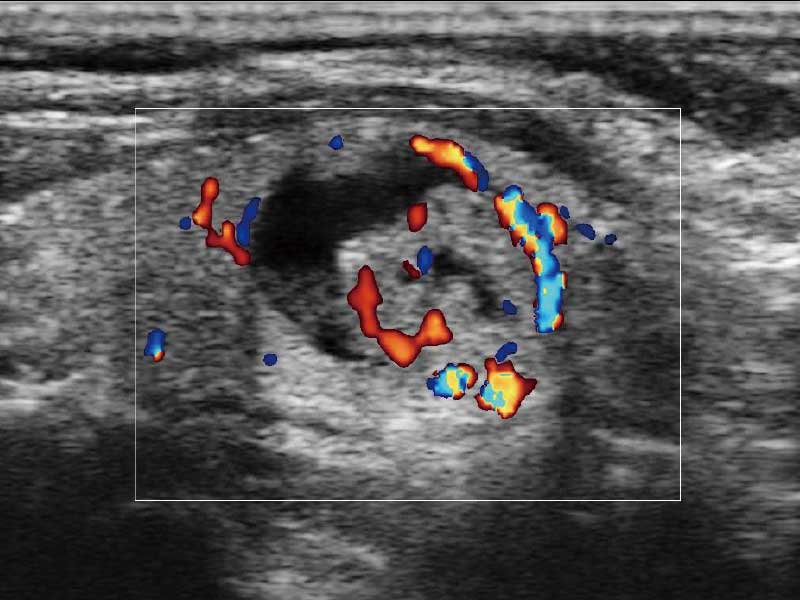

μ-Scan微米成像、空间复合成像、高分辨率血流成像。